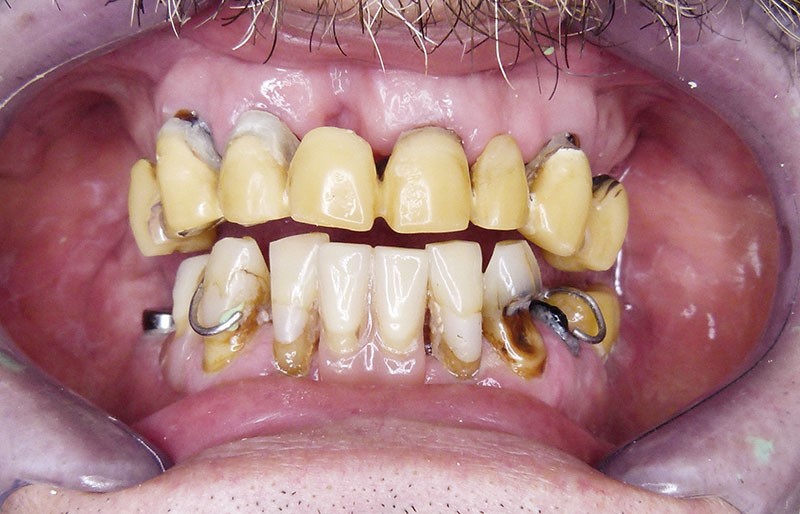

Des piliers multiunit Cortex® (Co Mua) sont vissés sur les implants, et l’ensemble est mis en charge immédiate par un bridge provisoire en résine acrylique renforcé au composite (fig. 3).